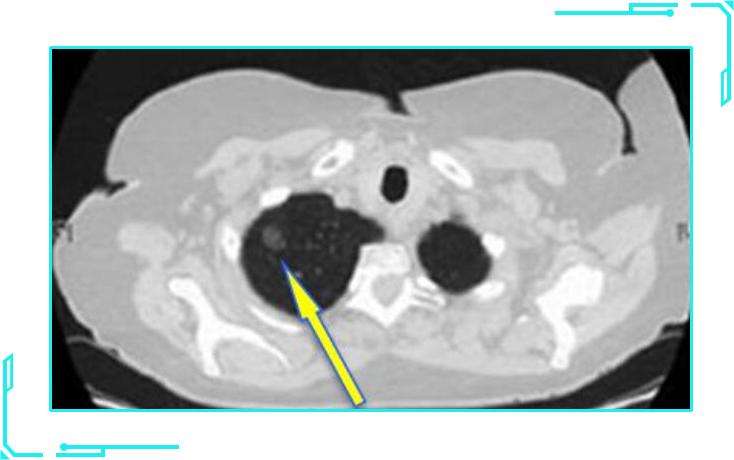

3纯实性结节

纯实性结节类似于单独分离的蛋黄,是一个实性且密度较高的病灶。